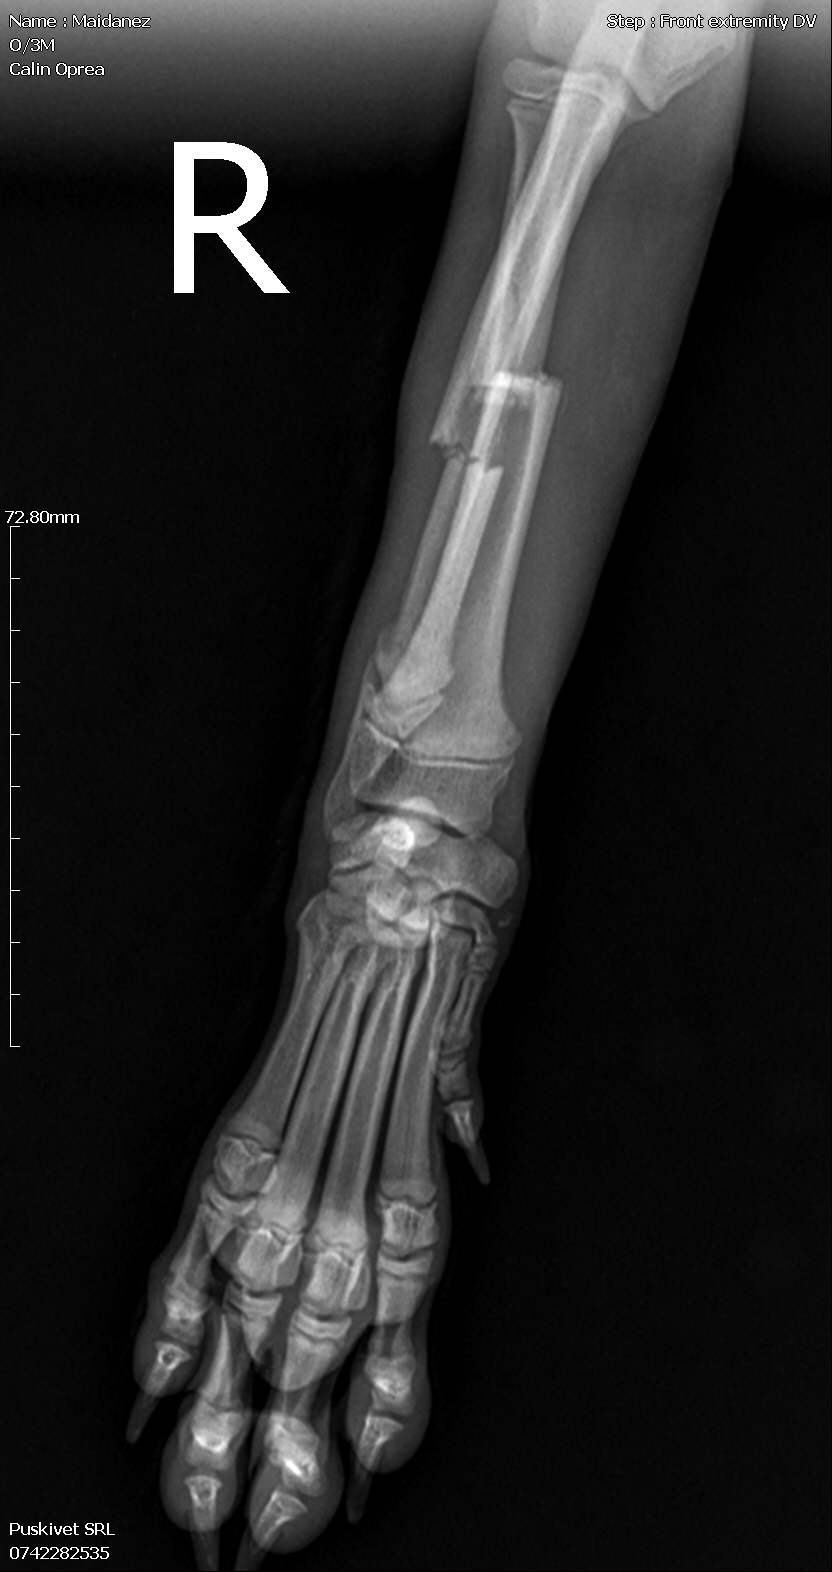

Le jour de l’An, une famille l’a trouvé seul, blessé et complètement démuni. Une radio a révélé une fracture à la patte avant droite. Il a été opéré, soigné et entouré avec beaucoup de douceur. Aujourd’hui, il a parfaitement récupéré et mène une vie tout à fait normale : il court, joue et profite de chaque instant.